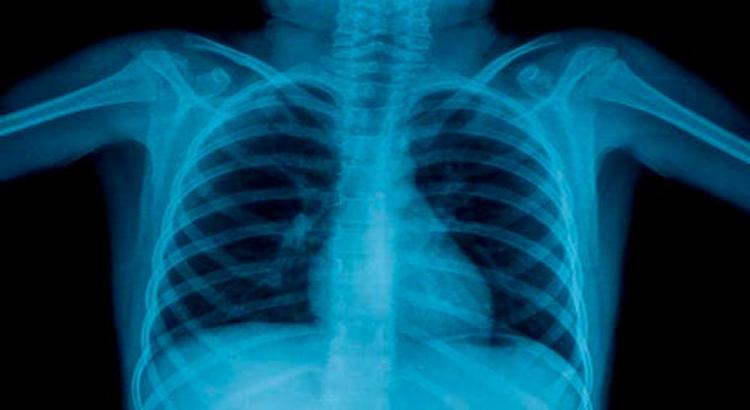

Süni intellekt rentgenoqrafiyadan insanın yaşını təxmin edir

Alimlər insanın bioloji yaşını təyin etmək üçün döş qəfəsinin rentgen şüalarını oxuya bilən süni intellekt (AI) modeli hazırlayıb. Yaponiyanın Osaka Metropolitan Universitetinin tədqiqatçıları müəyyən ediblər ki, süni intellektin proqnozlaşdırdığı yaş insanın həqiqi yaşı ilə müqayisədə nə qədər çox olarsa, fərdlərin xroniki xəstəliyə tutulma ehtimalı bir o qədər yüksəkdir. Tədqiqatın müəlliflərindən olan Yasuhito Mitsuyamanın sözlərinə görə, nəticələr göstərir ki, döş qəfəsinin rentgenoqrafiyasına əsaslanan görünən yaş xronoloji yaşdan kənarda sağlamlıq vəziyyətini dəqiq şəkildə əks etdirməyə qadirdir. Xroniki xəstəliklərin şiddətini, gözlənilən ömür müddətini və mümkün cərrahi ağırlaşmaları proqnozlaşdırmaq üçün tətbiq daha da inkişaf etdiriləcək.

Tədqiqatçılar döş qəfəsinin rentgenoqrafiyasını və ya rentgen şüalarını oxuya bilən süni intellekt modeli yaratmaq üçün sağlam fərdlərdən alınan 67 min döş qəfəsinin rentgenoqrafiyasından istifadə ediblər. Sağlam fərdlər üçün süni intellektin təxmin etdiyi yaş ilə insanın xronoloji yaşı arasında güclü korrelyasiya əldə olunub. Onlar, həmçinin məlum xəstəlikləri olan insanların döş qəfəsinin 34 mindən çox rentgenoqrafiyasını sınaqdan keçiriblər. Süni intellektin proqnozlaşdırdığı bu tətbiqin hipertoniya, xroniki obstruktiv ağciyər, qaraciyər və xroniki böyrək çatışmazlığı kimi bəzi xəstəliklər üçün insanın həqiqi yaşı ilə müqayisədə daha yüksək yaş verdiyi təsbit edilib. Ancaq pnevmoniya kimi kəskin xəstəliklər üçün korrelyasiya daha aşağı olub. Bu nəticə o deməkdir ki, süni intellekt döş qəfəsinin rentgenoqrafiyasında kəskin deyil, xroniki dəyişiklikləri ələ keçirir, bu ağlabatandır, çünki yaşlanma zamanla yığılan xroniki dəyişikliklərin nəticəsidir.

Alimlərin fikrincə, bu süni intellekt modeli yaşa bağlı xəstəliklərin göstəricisi ola, erkən diaqnoz və müdaxiləyə kömək edə bilər.